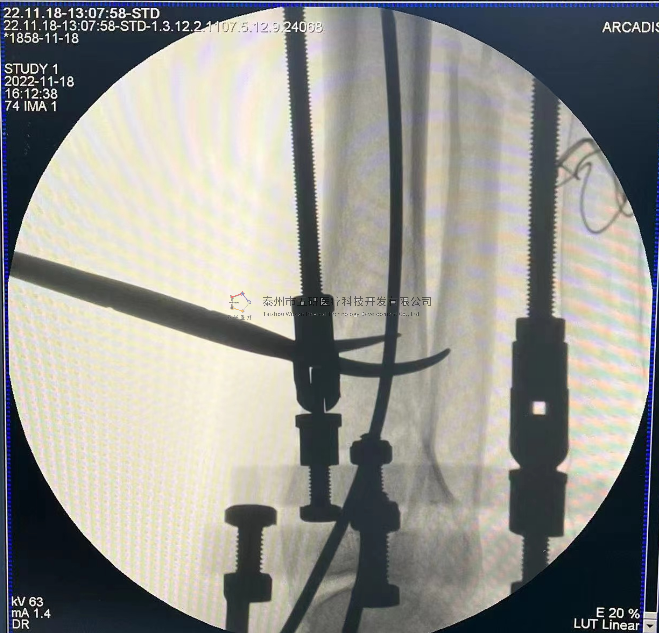

// 踝關(guān)節(jié)

本病例由中國中醫(yī)科學(xué)院望京醫(yī)院骨關(guān)二提供(術(shù)者:支架主任蔣主任)

【基本資料】患者,男,41歲

本病例踝關(guān)節(jié)骨折。手術(shù)名稱:左踝關(guān)節(jié)骨折外固定支架手術(shù)

【手術(shù)資料】